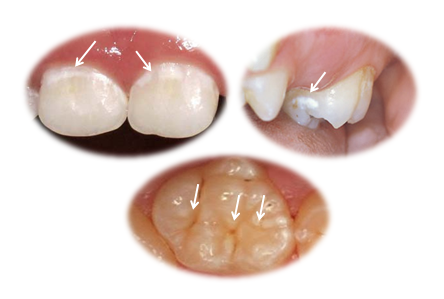

Prvi znaci topljenja gleđi su bele mrlje.(Slika 1.) One se lako uočavaju na vidljivim i griznim površnama zuba, i to su mesta gde se najpre i najbrže razvija rani karijes, naziva se još i „cirkularni karijes“, i od njega već do druge godine oboljeva 15%, a u periodu 3 – 5 godina čak 50% naše dece. Ovakva lokalizacija se lako uočava na običnom pregledu i pravovremenom intervencijom je moguće lako da se spreči pucanje.

Poseban problem predstavlja topljenje zuba na bočnim površinama koje su u međusobnom kontaktu. Proces topljenja se tu odvija neprimetno, uglavnom nema bilo kakvih simptoma, poput osetljivosti(mlečni zubi su slabije osteljivi, ali i kod stalnih obično ide bez simptoma). Kada zubna gleđ dovoljno oslabi, prilikom najobičnijih pokreta žvakanja dolazi do pucanja zuba i lezija postaje vidljiva.(Slika 2.). I to izgleda kao da je „potpuno zdrav zub preko noći oboleo“.

Ovakve defekte na mlečnim zubima je često veoma komplikovano rešavati klasičnim „plombiranjem“, već se moraju postaviti posebne fabričke krunice(Slika 3.).